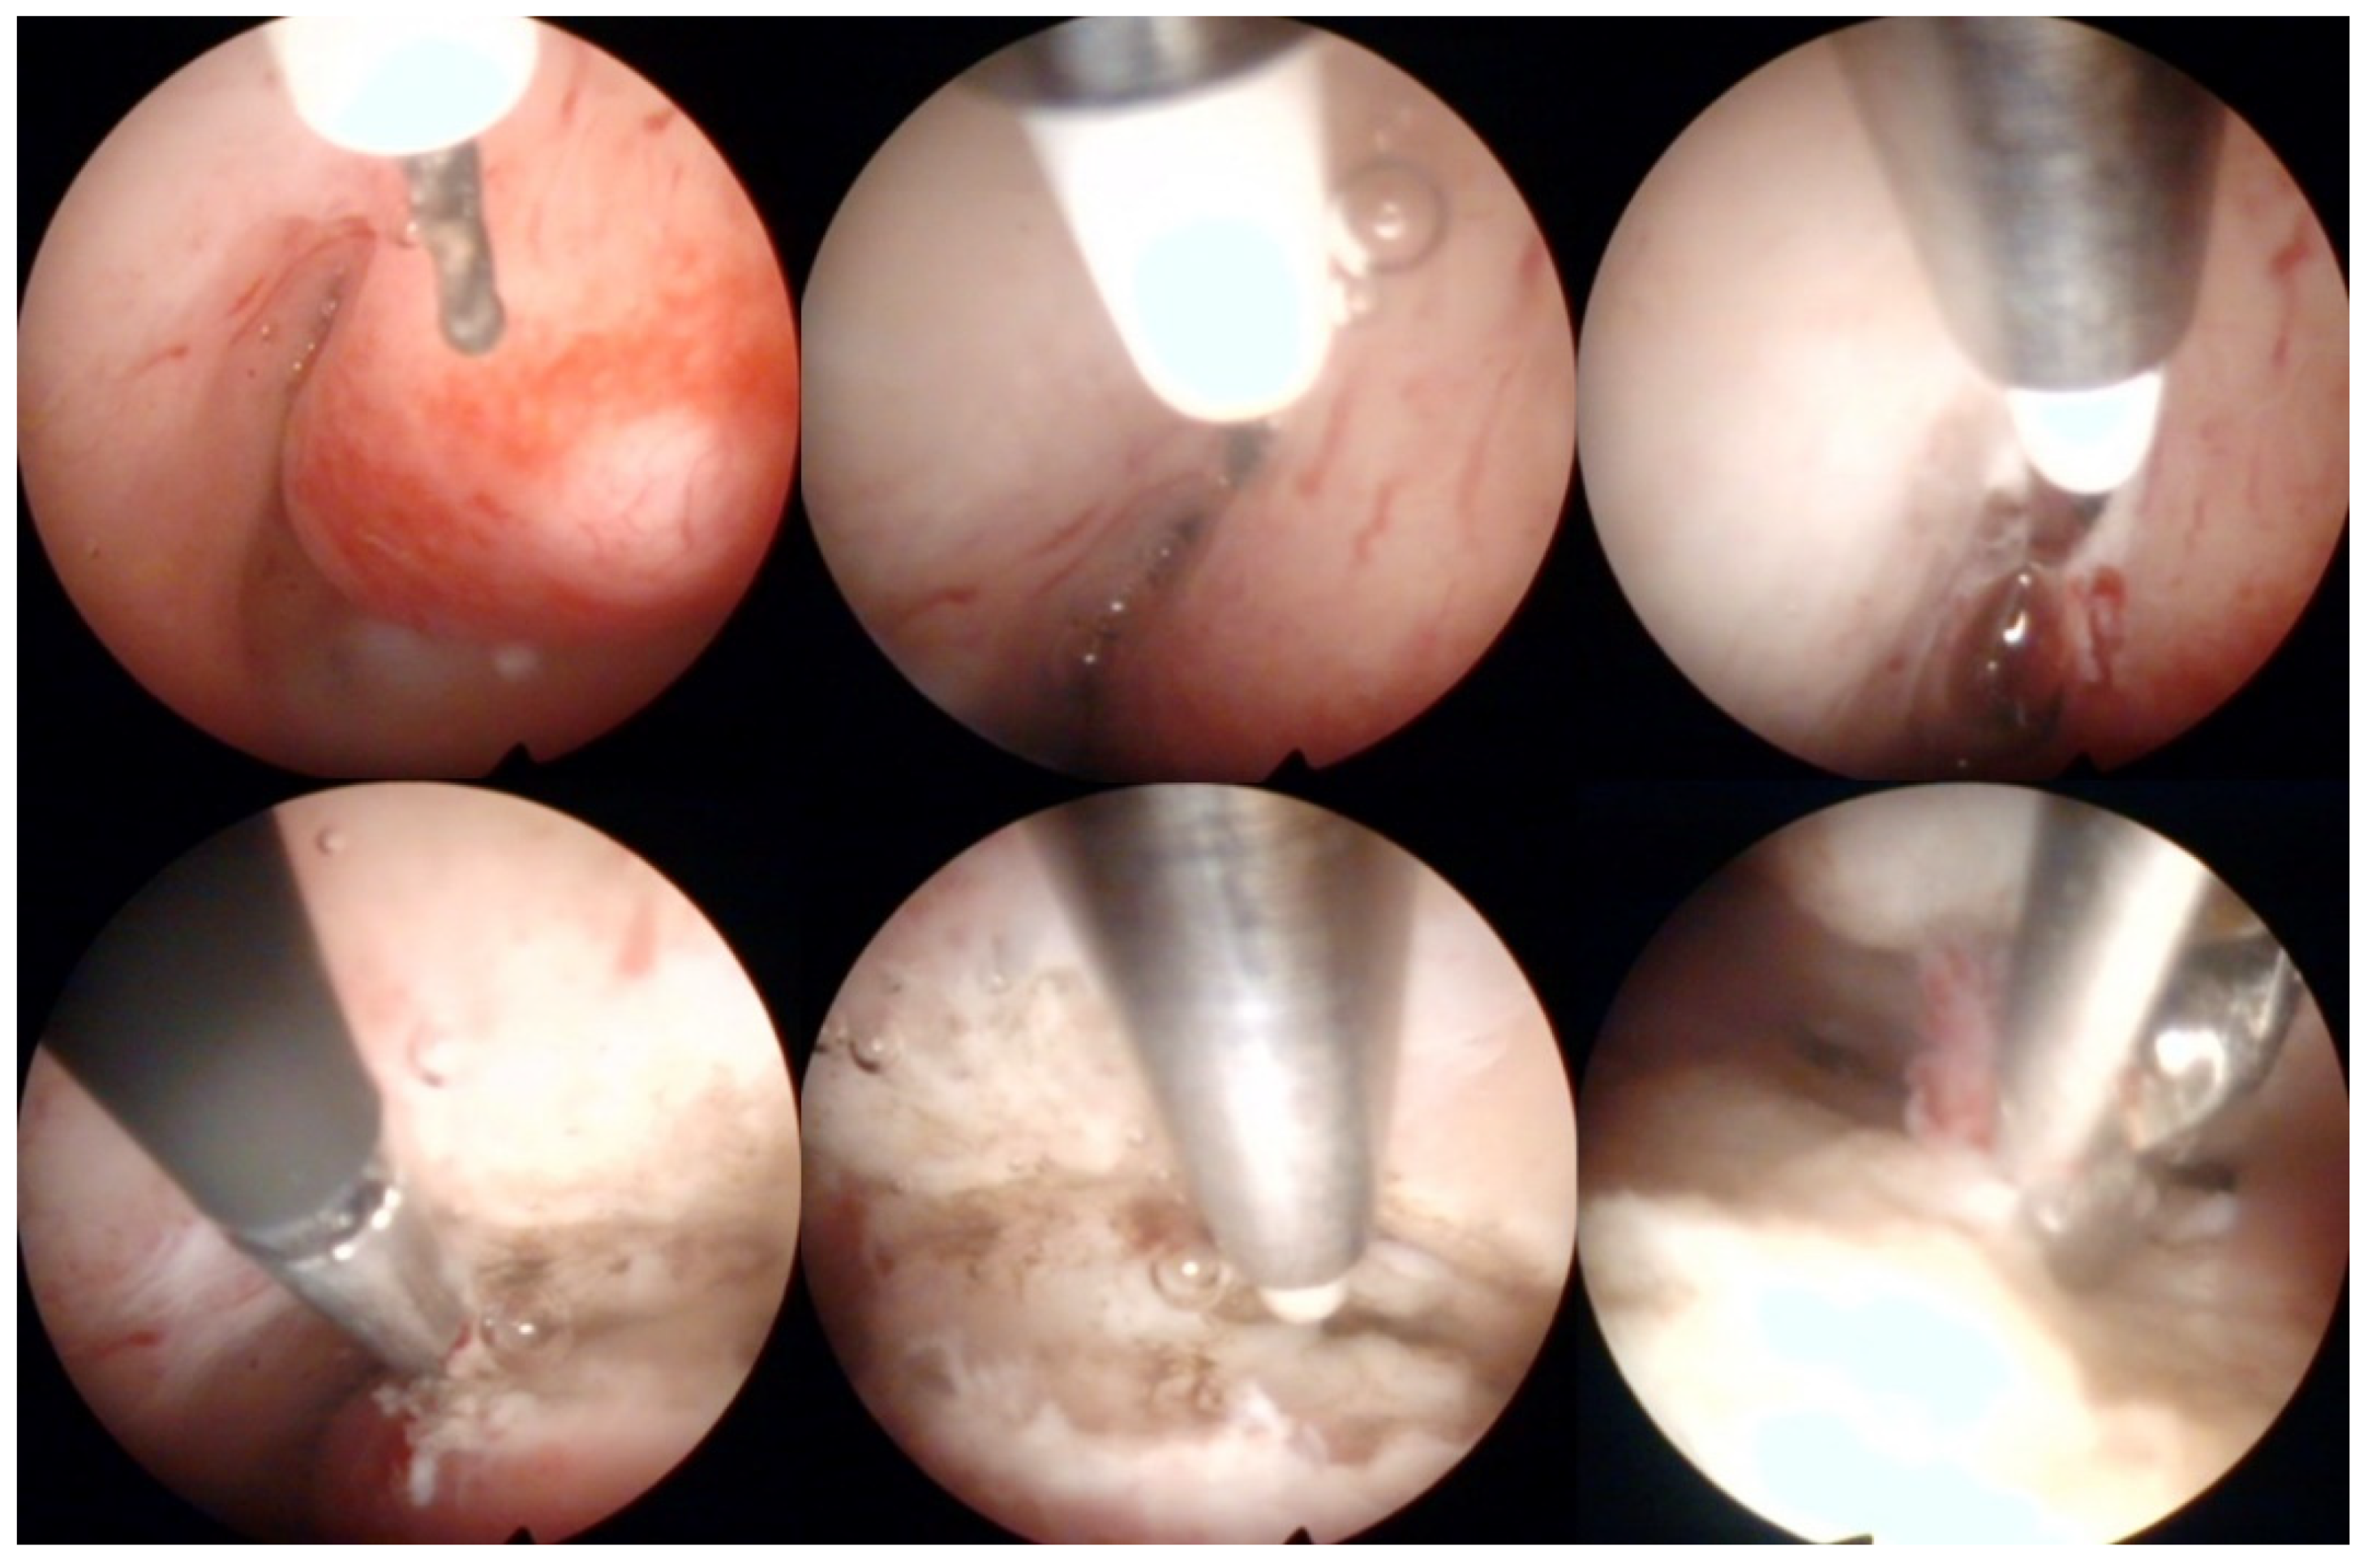

Operative hysteroscopy uses mechanical, electrosurgical, and laser instruments to treat intracavitary pathologies. The introduction of the small-diameter coaxial bipolar electrode (Versapoint, Gynecare, Ethicon, NJ, USA) in 1999 was a milestone for outpatient operative hysteroscopy (Figure 4) [47]. The development of miniaturized mechanical instruments with small diameter scopes and working channels with continuous flow systems enabled the “see-and-treat” approach without general anesthesia [32,34,48,49,50]. Wortman et al. [51] confirmed that major operative hysteroscopic surgery could be performed in an office-based setting resulting in a 98.8% rate of “satisfied” or “very satisfied” patients. Both outpatient (73%) and inpatient (80%) hysteroscopic polypectomy offer comparable success rates, as determined by the patients’ subjective bleeding and QoL assessment after six months [52]. However, procedure failure is higher (19% vs. 7%), and acceptability is lower (83% vs. 92%) with outpatient compared to inpatient polypectomy [52]. An essential aspect of hysteroscopic surgery is a very high level of physician satisfaction (e.g., 95% reported in [53]) associated with this approach. Factors such as incomplete resection and recurrence of the pathology decrease the acceptability of hysteroscopic surgery [38,52].

Figure 4.

Operative hysteroscopic removal of an endometrial polyp (mean diameter 13 mm) by Versapoint system (Gynecare, Ethicon Inc., Raritan, NJ, USA). Intraoperative photographs by F.B. and S.F.